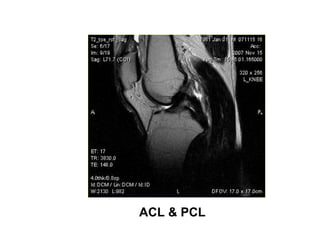

ACL & PCL

ACL PCL

MRI KHÔÙP GOÁI

GIAÛI PHAÃU BÌNH THÖÔØNG